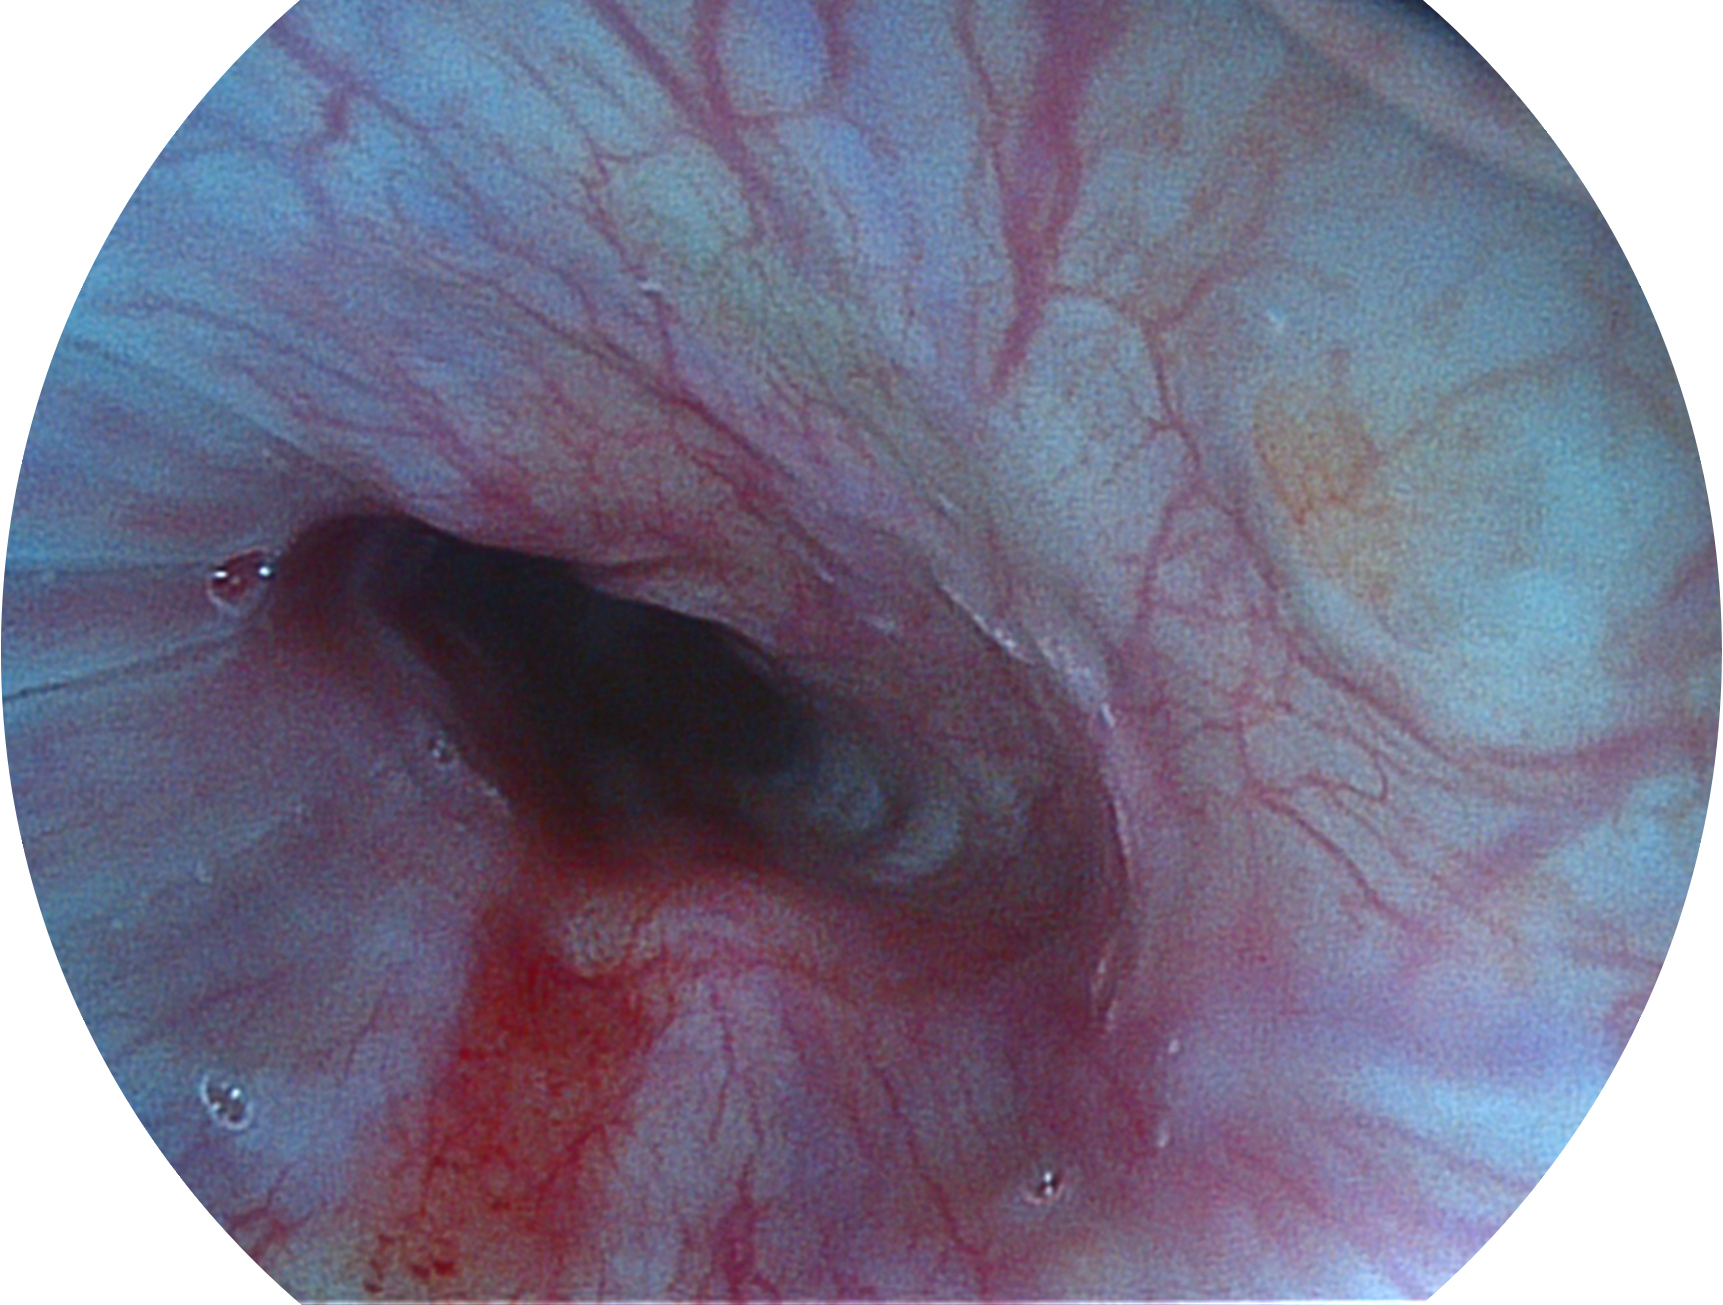

环球UG官网新开发的内镜染色技术,主要是基于多波长LED 光源的开发,VLS-55Q 四波长LED 光源是由四个不同颜色的LED光按照相应照明模式所规定的特定发光比例进行合束后形成,合束后形成的照明光的光谱由红光、绿光、蓝光及蓝紫光这四个不同的波段范围构成。具有更高光谱自由度,通过光谱比例的控制,实现了聚谱成像技术,英文全称为“Spectral Focused Imaging, SFI”,缩写为“SFI”和光电复合染色成像技术,英文全称为“Versatile Intelligent Staining Technology, VIST”,缩写为“VIST”。